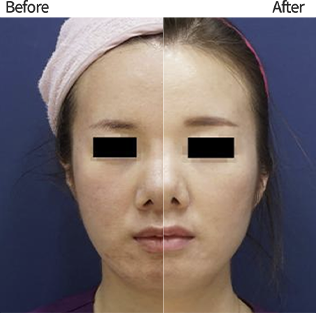

ลดความหย่อนคล้อย

ลดความหย่อนคล้อย